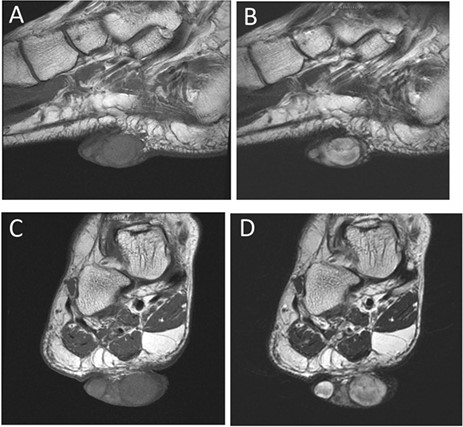

The patient was a 53-year-old female, who had noticed an asymptomatic, skin-colored nodule in her right sole over 30 years prior. The tumor was elastic and soft, measured 5.5 × 4.0 cm and rose up from the plantar aspect of her foot (Fig. 1A and B). Magnetic resonance imaging (MRI) revealed a tumor from the dermis to the subcutaneous fat of the plantar aspect. The tumor was homogeneously isointense relative to the skeletal muscle on T1-weighted images and hyperintense on T2-weighted fat-suppressed images. The tumor contained internal heterogeneous cystic lesions (Fig. 2A–D).

(A) Sagittal view on MRI T1. (B) Sagittal view on MRI T2. (C) Frontal view on MRI T1. (D) Frontal view on MRI T2 (green arrow indicates the tumor).